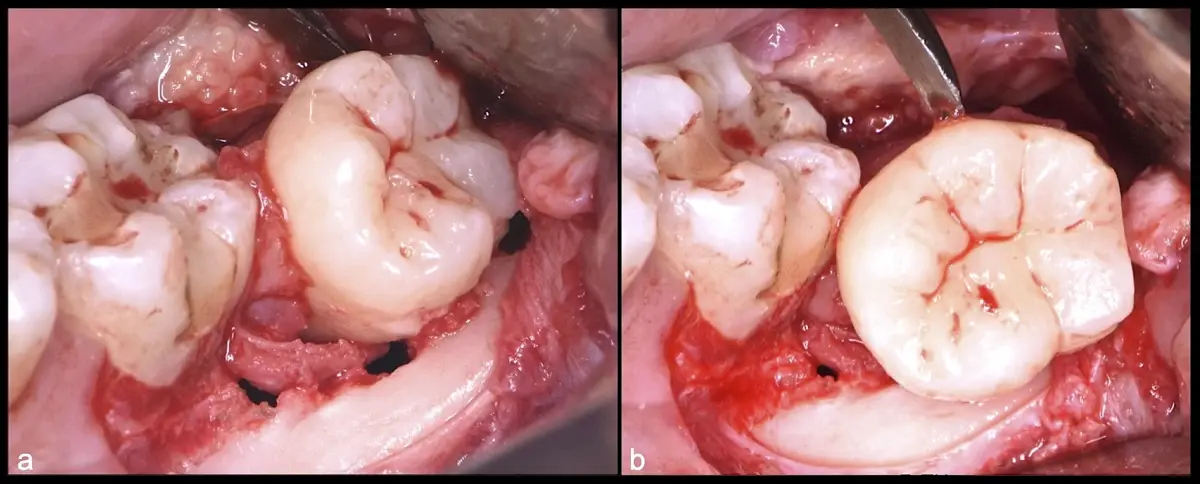

Es imprescindible conocer la ubicación de la tercera molar. Se puede emplear, adicionalmente a la evaluación clínica, herramientas radiográficas (panorámica y periapical) y tomográficas (Cone beam) para determinar la posición, grado de retención y proximidad a estructuras vecinas de riesgo como el nervio dentario inferior y así evitar lesiones (Figura 1).

El procedimiento se inicia colocando anestesia troncular para bloqueo del nervio dentario inferior y sus ramas. Luego, se establecerá el diseño de acceso según la disposición de la molar a extraer. Para fines didácticos, se explicará cómo se realizaría la extracción de la molar de la Figura 1: se realiza una incisión horizontal a nivel de la zona retromolar hasta llegar a distal de la segunda molar, continuándose con una incisión intrasurcular hasta mesial de la segunda molar, finalizando con una incisión vertical a espesor total hasta llegar a la línea mucogingival (Figura 2).